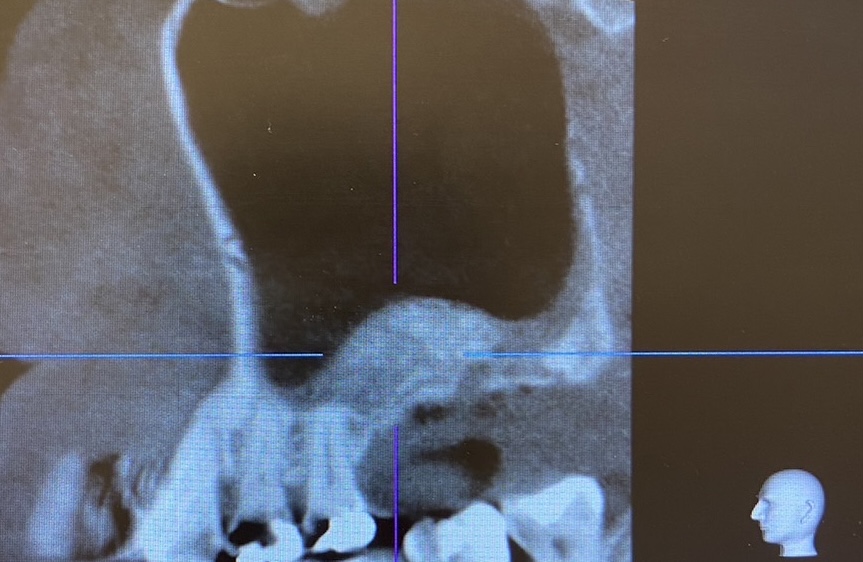

Before

寝屋川市の歯科医院からの紹介の患者様です。

上顎の骨が少なく、インプラントを行えないためサイナスリフト(骨造成)をおこないました。

当院でサイナスリフトを行い、かかりつけの元の医院でインプラント治療を行う予定です。

| 症例名 | 上顎の骨造成(サイナスリフト) |

| 年齢 | 50 | 性別 | 男性 | 地域 | 寝屋川市 |

| 治療内容 | サイナスリフト | ||||